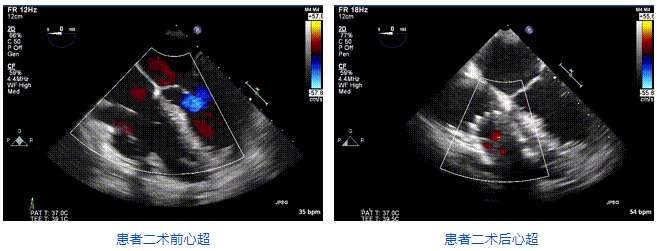

2021年12月24日,復(fù)旦大學(xué)附屬中山醫(yī)院葛均波院士團(tuán)隊(duì)成功應(yīng)用LuX-Valve Plus為一例極重度三尖瓣反流(TR)合并房顫、房缺的患者完成了經(jīng)血管三尖瓣置換術(shù),這是在前基礎(chǔ)上,本周完成的第三例經(jīng)血管三尖瓣置換手術(shù),葛均波院士、周達(dá)新教授等與心外科魏來教授、賴顥教授,心超室的潘翠珍教授、李偉教授及麻醉科的郭克芳教授共同完成了本周手術(shù),均獲得圓滿成功!患者術(shù)后超聲顯示無TR,臨床癥狀明顯改善。本周手術(shù)的成功也為L(zhǎng)uX-Valve Plus救治性臨床研究添上了濃墨重彩的一筆。

本周三例接受LuX-Valve Plus經(jīng)血管三尖瓣置換術(shù)的患者中,第一例患者為冠狀動(dòng)脈旁路移植術(shù)+Bentall+二尖瓣成形術(shù)后;第二例患者為永久起搏器植入術(shù)后,存在跨三尖瓣導(dǎo)線;第三例患者合并房顫、房缺及左心耳封堵術(shù)后。

三例患者入院后,葛均波院士團(tuán)隊(duì)周達(dá)新教授、潘文志教授、張?jiān)床┦?、陳莎莎博士及心超室的潘翠珍教授、李偉教授?duì)患者的情況進(jìn)行詳細(xì)評(píng)估和討論,最終決定為三例患者選擇LuX-Valve Plus40mm、50mm和50mm型號(hào)的瓣膜進(jìn)行手術(shù)治療。手術(shù)后即刻拔除氣管插管,術(shù)后患者三尖瓣反流癥狀得到顯著改善,復(fù)查心超結(jié)果顯示人工三尖瓣瓣膜支架固定穩(wěn)定,瓣葉關(guān)閉形態(tài)未見異常,未見明顯反流。